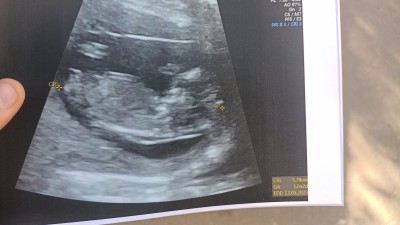

Kızlar cinsiyet tahmininde bulunur musunuz? ❣️

Gebelik haftası 12+2

Kiz gibi gözüküyor

Erkek gibi duruyor

Erkek bence canm